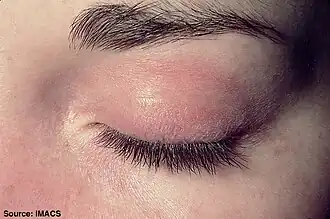

Heliotrope with swelling around the eyes

Heliotrope with swelling around the eyes -

Heliotrope

Heliotrope -

One form the rashes take is called "heliotrope" (a purplish color) or lilac, but may also be red. It can occur around the eyes along with swelling, but also occurs on the upper chest or back what is called the "shawl" (around the neck) or "V-sign" above the breasts and may also occur on the face, upper arms, thighs, or hands.[9] Another form the rash takes is called Gottron's sign, which is red or violet, sometimes scaly, slightly raised papules that erupt on any of the finger joints (the metacarpophalangeal joints or the interphalangeal joints).[9][10] Gottron's papules may also be found over other bony prominences including the elbows, knees, or feet. All these rashes are made worse by exposure to sunlight, and are often very itchy, painful, and may bleed.[10]